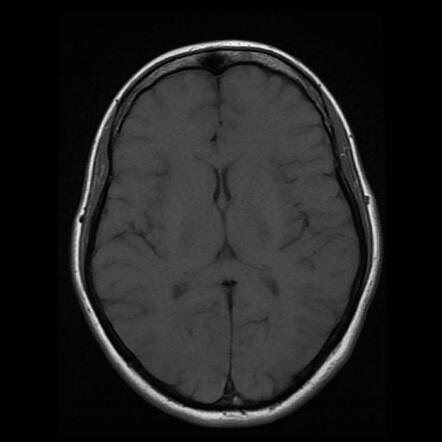

МРТ головного мозга: Расшифровка снимков и Интерпретация

Раздел: Визуальные уроки